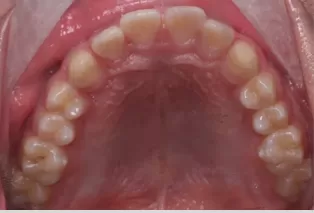

Intraoral photos